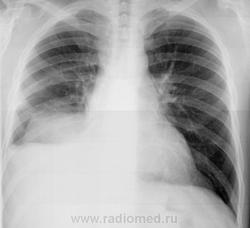

Случай из украинской глубинки. Молодой мужчина поступает в хирургическое отделение.

Вот первичный снимок...

Снимки консультированы мной по Интернету. Рекомендована плевральны пункция.

Последняя проведена. Удалено около 1,5 жидкости соломенного цвета. Образцы переданы на исследование.

Плеврит с тенденцией к осумкованию междолевому, медиастинальному. Но я обратил внимание на косые паракостальные линии, прямо как у недавно выставляемой мной бабульки с такими же теперь понятными мне линиями.

Если имеется температура, нет "острого живота", а результаты жидкости будут получены в понедельник, то можно смело направить пациента в тубстационар.На снимке из архива имелся наддиафрагмальный выпот, в 3-м межреберье справа и чуть ниже избыточный легочный рисунок. Слева очаги в верхушке и1-м/р. Желаю больному выздоровления. С уважением Nik

Ник, спасибо! На плотный очаг на верхушке слева тоже указывал в консультации, так что настороженность на туберкулезную этиологию присутствует.